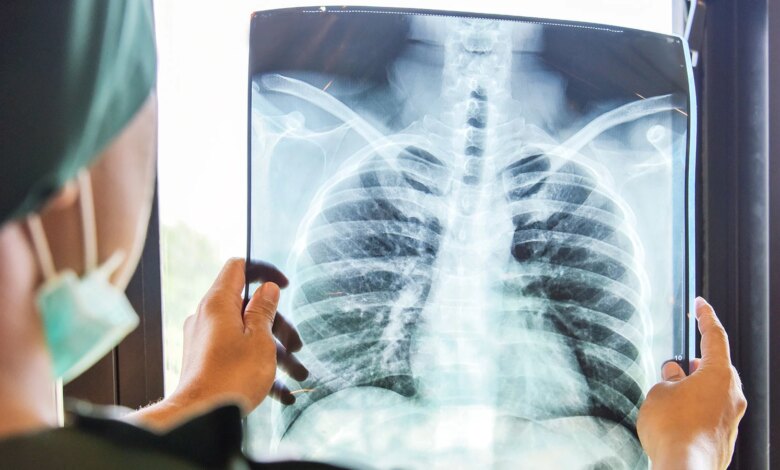

Dr. Yavuz, KOAH’ın amfizem ve kronik bronşitin birleşimi olduğunu ifade etti. Bu hastalık, akciğerdeki küçük hava odacıklarının harabiyeti sonucu hava yollarının daralmasıyla ortaya çıkıyor.

KOAH tanısında en temel yöntemin Solunum Fonksiyon Testi (SFT) olduğunu ifade eden Dr. Yavuz, hastalığın tamamen tedavi edilemeyeceğini ancak ilerlemesinin durdurulabileceğini vurguladı.